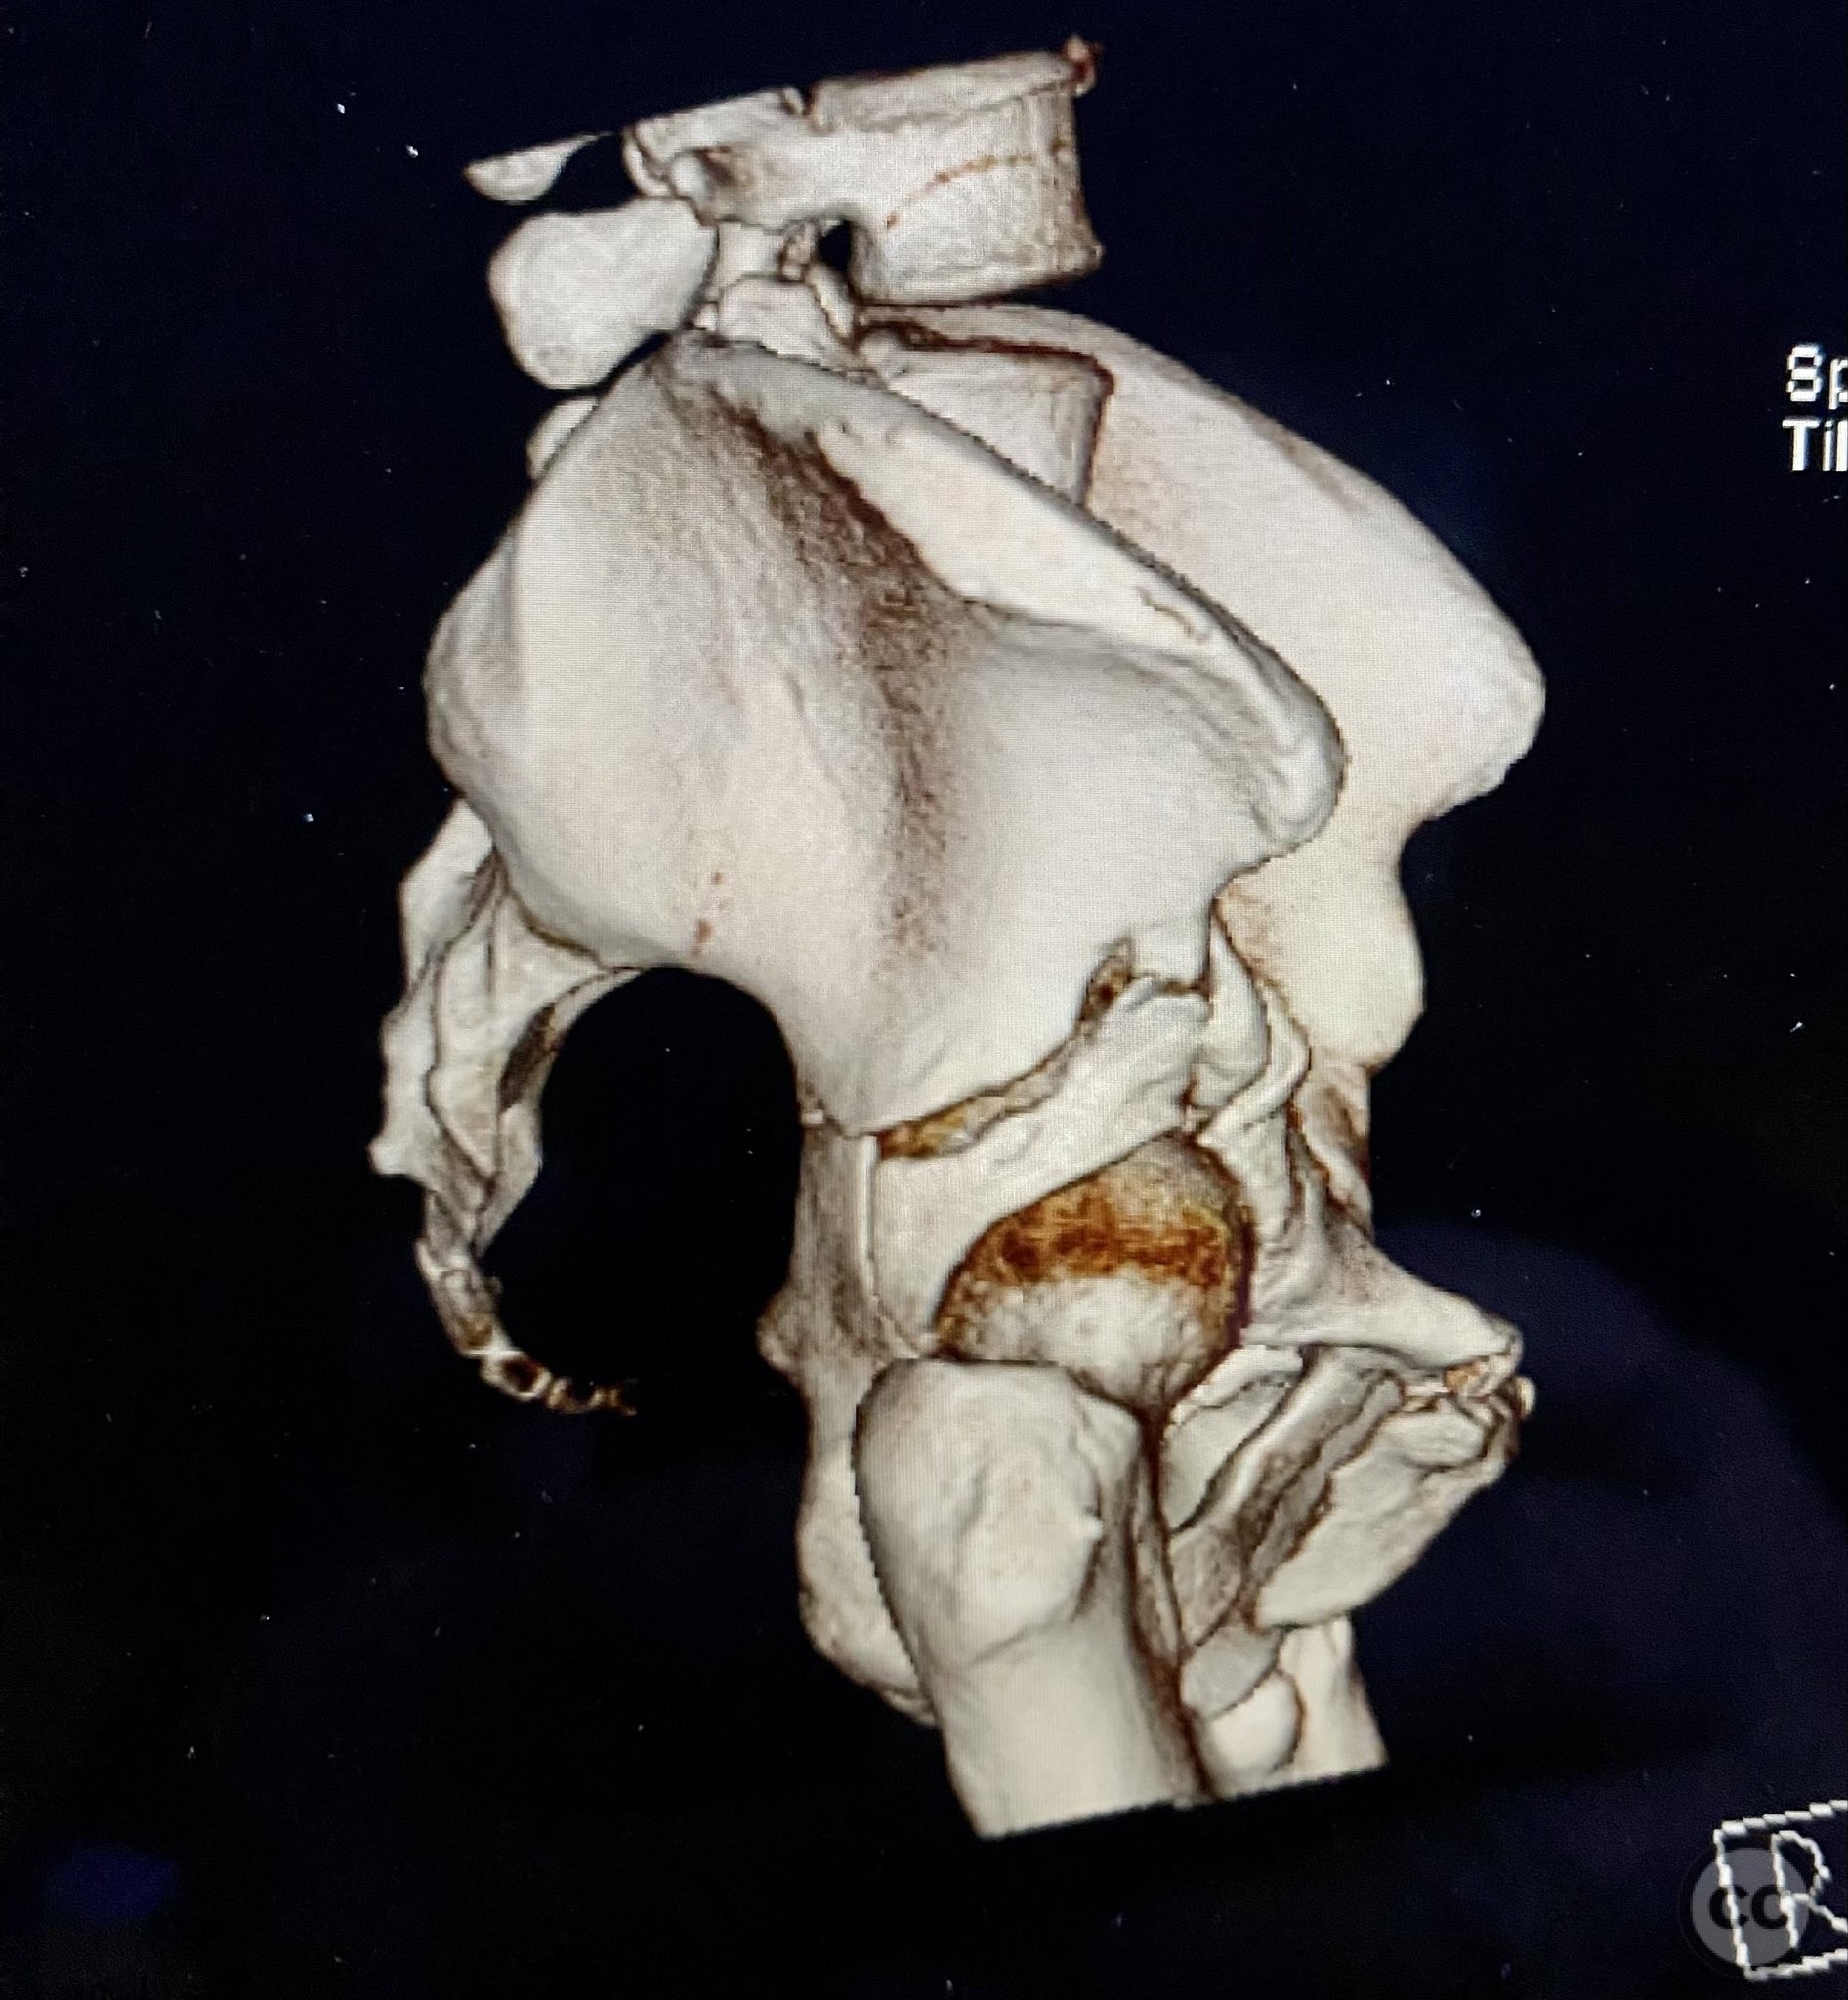

Clinical and radiological findings:  The patient sustained a complex both column acetabular fracture, AO/OTA 62C1, characterized by several large columnar fragments, an independent anterior inferior iliac spine (AIIS) fragment, a notable dome fragment predominantly attached to the posterior wall (PW) fragment, and a distinct parasymphyseal injury zone. Initial application of a pelvic binder resulted in increased displacement of the fracture fragments. Preoperative imaging, including surface renderings and multiplanar CT, demonstrated the independent AIIS fragment, detailed cortical surfaces, and the orientation of fracture planes. The majority of the acetabular dome was associated with the PW fragment, a critical detail for surgical planning and reduction.

Planning remarks:  The preoperative plan involved an ilioinguinal approach to facilitate direct visualization, cleaning, and reduction of the cortical and fracture surfaces. The reduction sequence was planned as follows: first, anatomical reduction and provisional fixation of the anterior column (AC) fragment using a 6-hole plate and lag screw; second, application of a 12-hole intrapelvic plate for additional stabilization; third, definitive stabilization of the posterior column (PC) and PW fragments with lag screws. No additional exposures were planned.